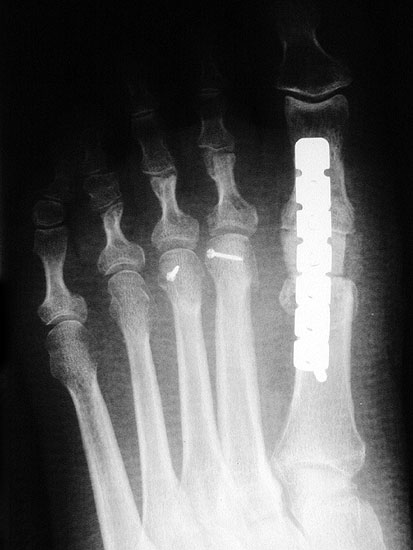

Die dorsoplantaren Röntgenaufnahmen zeigen eine Open-wedge Technik mit der normalerweise ein erhöhter intermetatarsaler Winkel gut zu korrigieren ist (Abbildung 3). Die Wirksamkeit einer Basisosteotomie ist umso größer, je proximaler diese durchgeführt wird. Je weiter distal die Osteotomie, umso geringer die Korrektur. Auf den postoperativen Bildern ist der distal unverändert große Abstand zwischen Metatarsale I und Metatarsale II erkennbar, bei gleichzeitiger Subluxation des Großzehengrundgelenks und dezentrierten Sesambeinen. Darüber hinaus finden sich initiale degenerative Veränderungen im Großzehengrundgelenk. Klinisch bestand eine hohe Weichteilspannung, bei verkürzter Extensor- und Flexor hallucis longus Sehne.  Daher wurde ein verkürzendes Verfahren zur Revision gewählt (Abbildung 4). Die Lapidusarthrodese stellt ein sehr zuverlässiges Verfahren zur Behandlung von Hallux valgus Rezidiven dar 9. Die Fusion des Tarsometatarsale-I-Gelenks kombiniert Stabilität mit einem hohen Korrekturpotenzial. Aufgrund der verfahrensimmanenten Verkürzung des ersten Strahls und der in diesem Fall bereits präoperativ vorhandenen Transfermetatarsalgie wurde die Entscheidung für eine verkürzte Weil-Osteotomie am zweiten bis fünften Strahl gefällt. Die Kombination beider Verfahren führte zu einem homogenen Metatarsale-Index und zu einer gleichmäßigen plantaren Druckverteilung 10. Die Hallux valgus interphalangeus Fehlstellung wurde mit einer Akin-Osteotomie korrigiert.